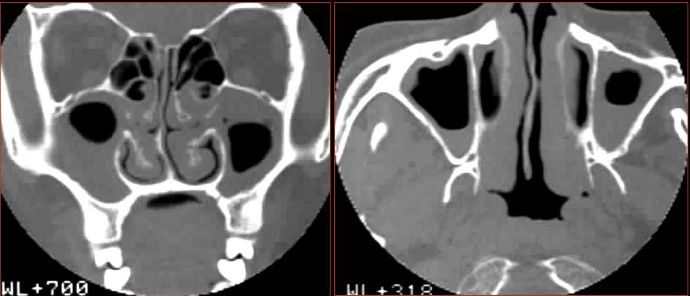

鼻息肉

◆ 原因不清,与慢性炎症、变态反应有关

◆ 起源于筛区,最常见是筛漏斗、中鼻甲和钩

◆ 临床表现:长期鼻堵、脓涕、复发鼻窦炎和/或头痛

CT表现

★ 平片无特征,可有鼻腔、鼻窦透光度下降

★ CT:单侧或双側鼻腔、鼻窦软组织团块影,软组织密度

★ 息肉生长处骨壁吸收

★ 少数骨壁増生硬化

★ 病变轻度增强

慢性多发鼻窦炎鼻息肉